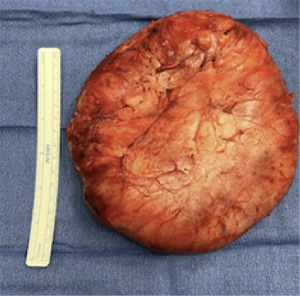

Two months later, the patient returned to the clinic with expansive growth of the left breast, similar in appearance and timeline to the right breast (Figure 5). An ultrasound was obtained that showed a large mass encompassing all four quadrants with homogeneous echotexture and scattered cystic spaces. Given a similar presentation to the other breast, a CNB was again performed. Using a 12-gauge BARD core device under direct ultrasound visualization, 5 samples were obtained. This resulted as a juvenile fibroadenoma, which was concordant with imaging. The patient again underwent left breast excisional biopsy (Figure 6). The incision, dissection, and closure were nearly identical to her contralateral surgery. Final pathology resulted as juvenile fibroadenoma, PASH, and fibrocystic changes (Figure 7) as confirmed by two pathologists.